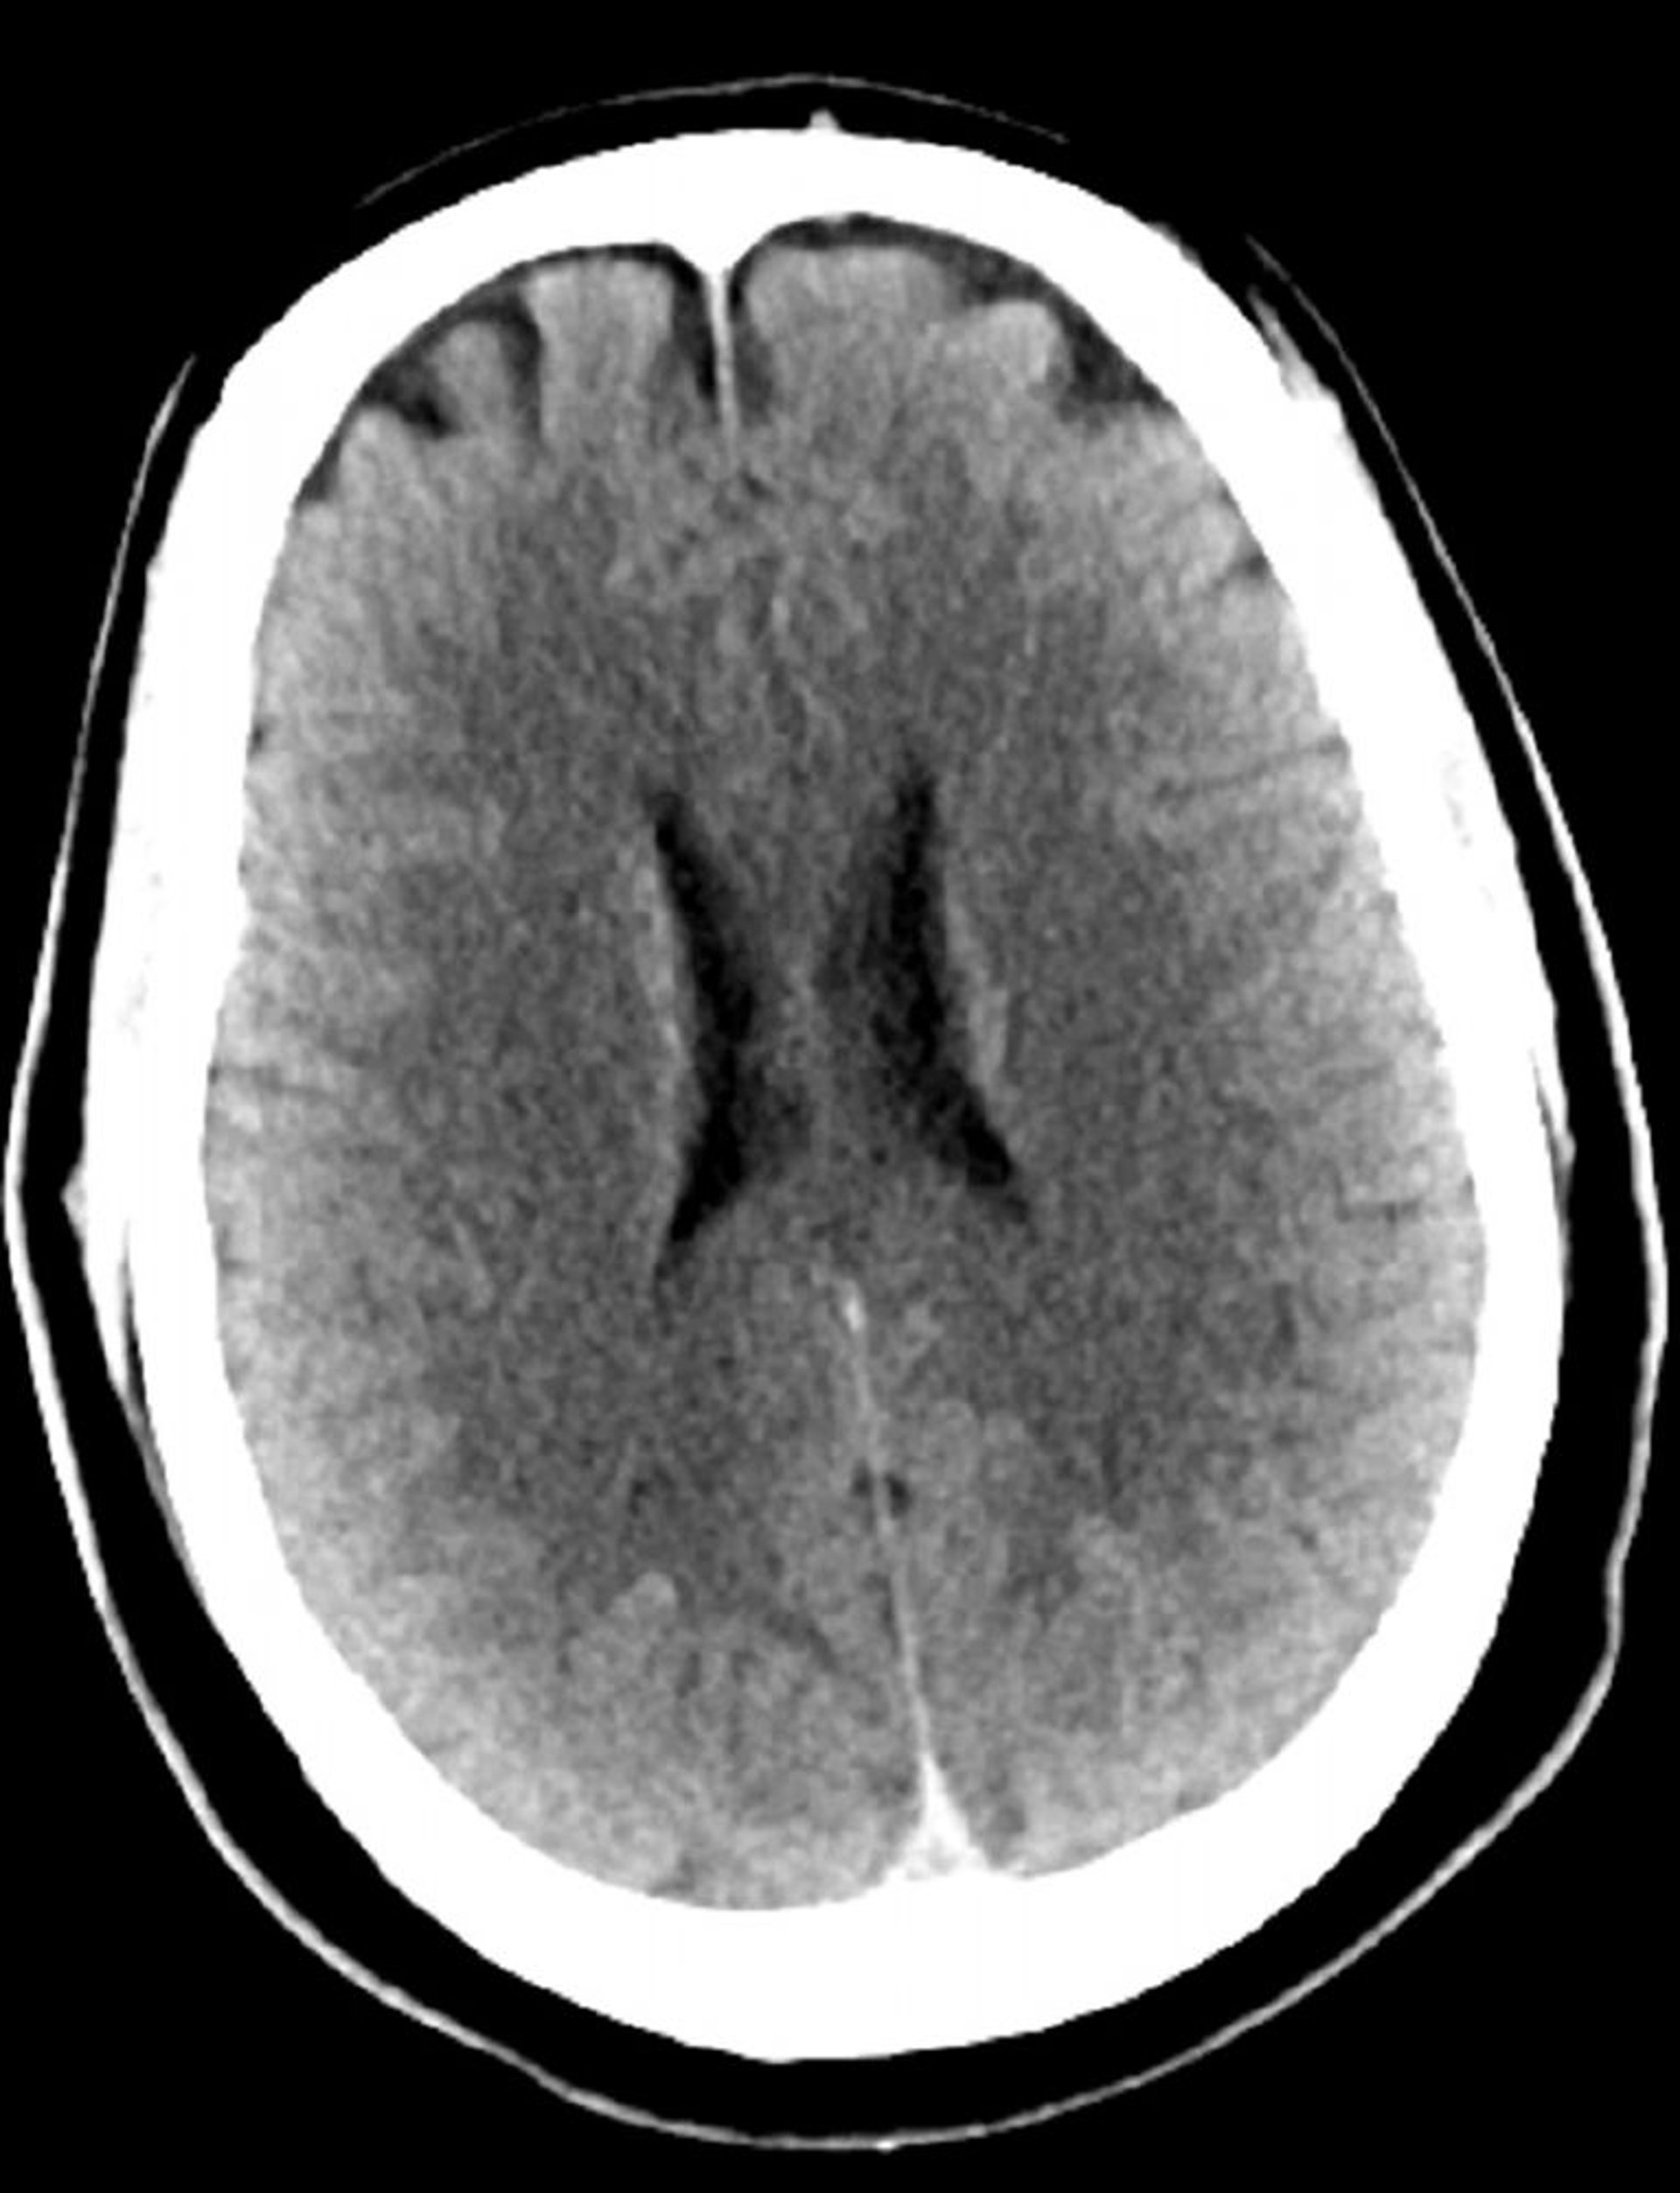

Normal Head CT Scan (Adult, Age 30) – Slide 3

This image is a normal CT scan of the head of a young adult aged 30. There is no intra- or extra-axial fluid or hemorrhage. Grey-white differentiation is preserved. Ventricular size and sulcal pattern are normal.